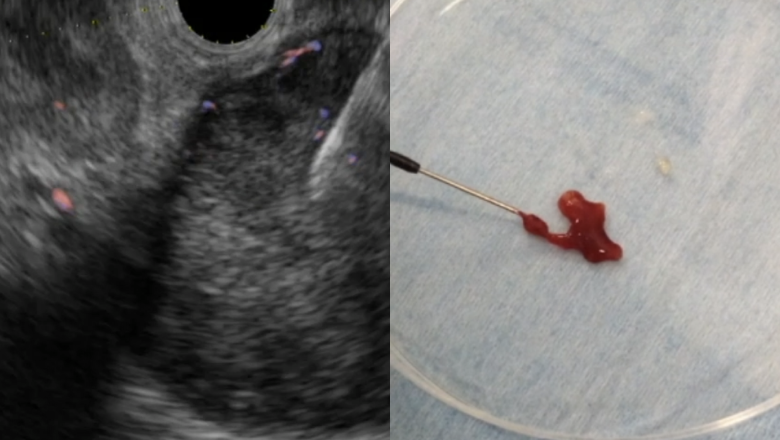

超音波内視鏡を用いた診断・治療